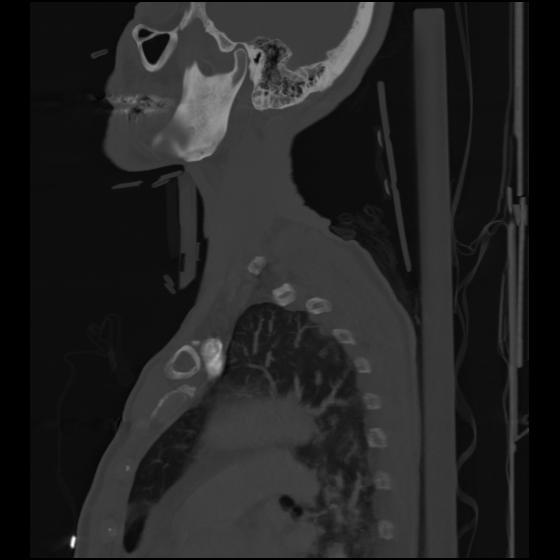

24 ANGIO,CE,Sag-MIP,5.000,ANGIO,Sag-MIP,